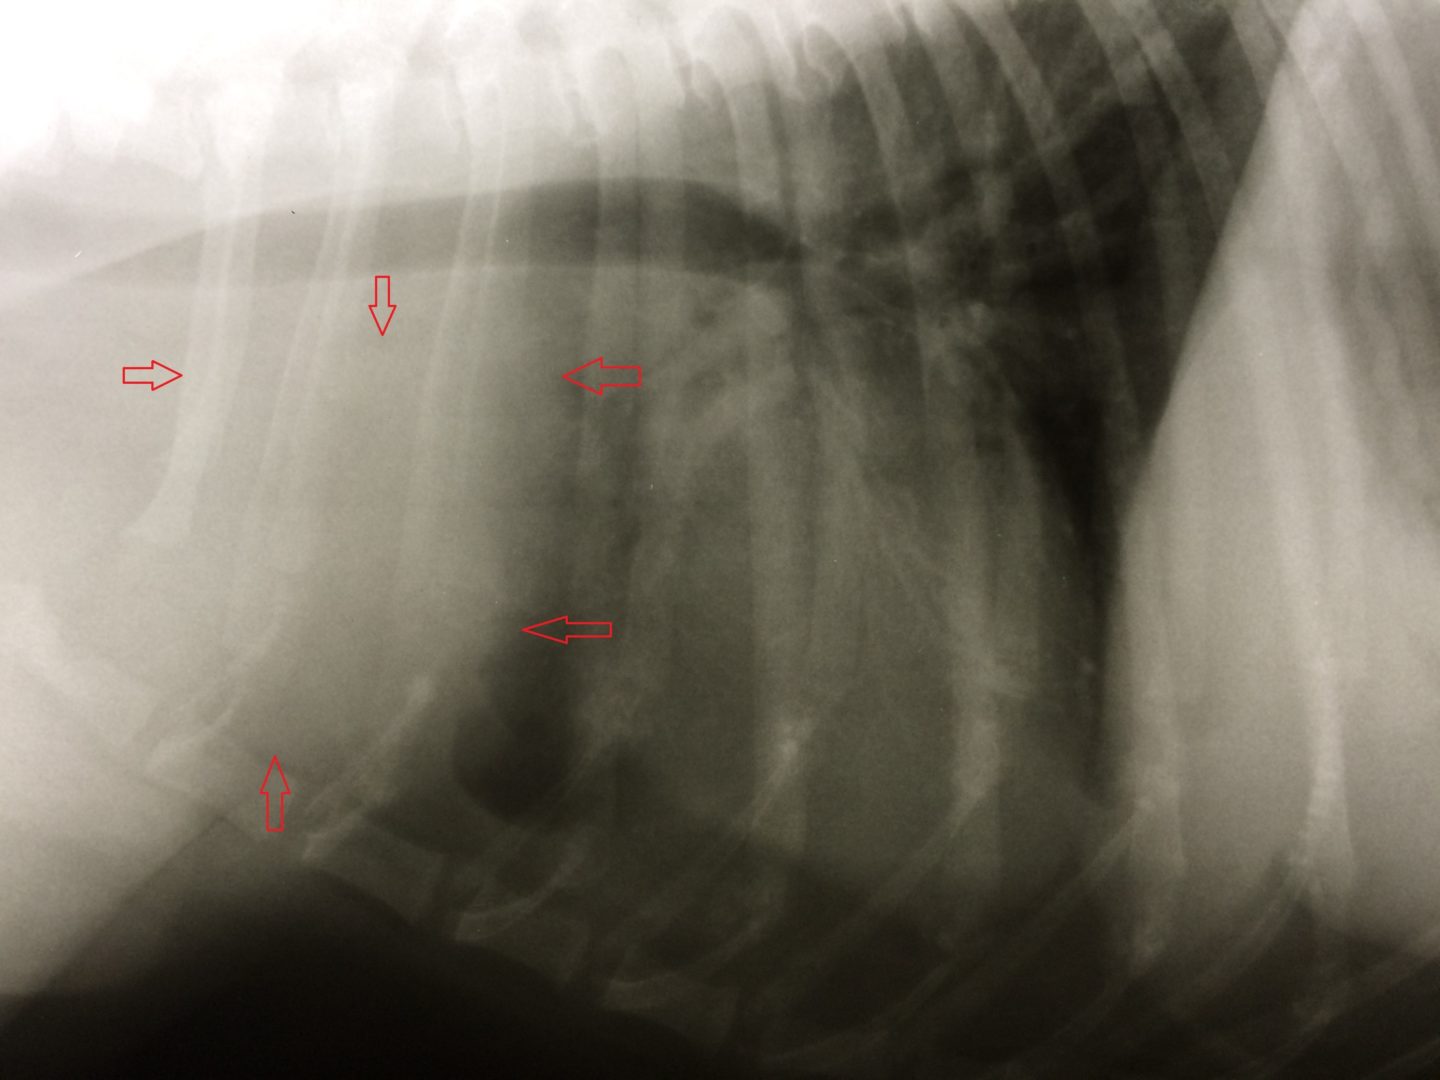

Die Analdrüsen und die äußerlich tastbaren Lymphknoten waren unauffällig. Daraufhin wurden Röntgenaufnahmen von Brust- und Bauchraum angefertigt. Im Brustkorb befand sich vor dem Herzen eine tennisballgroße Zubildung. Zur Diagnosestellung wurde dieser Tumor unter Ultraschallkontrolle mit einer Spritze punktiert und Zellmaterial gewonnen. Dieses Feinnadelaspirat wurde zu einem spezialisierten Tierpathologen geschickt. Der Befund: „Malignes Lymphom“. Das maligne Lymphom kann in einen B- und T-Zell-Typ eingeteilt werden, je nachdem welche Lymphozytenfraktion betroffen ist. In diesem Fall war es das schwieriger zu therapierende T-Zell-Lymphom. Die Ultraschalluntersuchung des Bauchraumes zeigte keine Veränderungen im Bereich von Leber, Milz und den anderen Lymphknoten des Bauches.